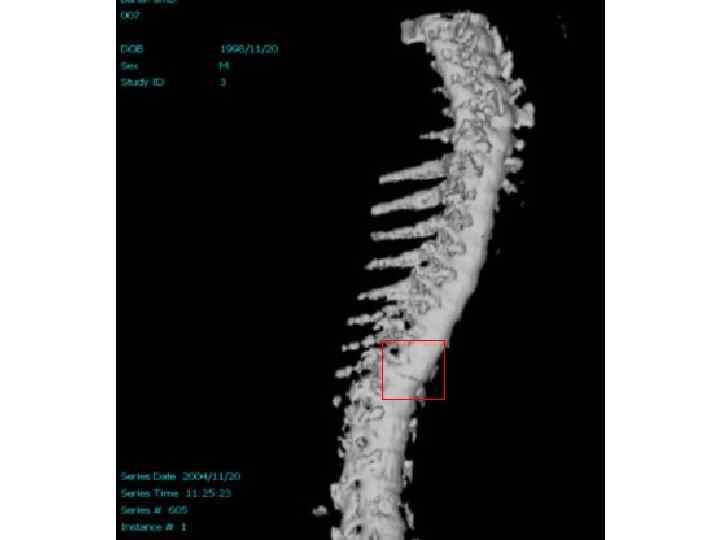

Методы диагностики поражения опорной системы человека 1. 2. 3. 4. Рентген, КТ, Радиоизотопная диагностика, Остеоденситометрия